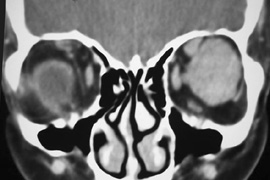

Fig. 16. A. Patient with right orbital cellulitis. B. Coronal CT scan demonstrating subperiosteal abscess formation from frontal and ethmoidal sinusitis. C. Frontoethmoidal orbitotomy incision marked for abscess drainage.